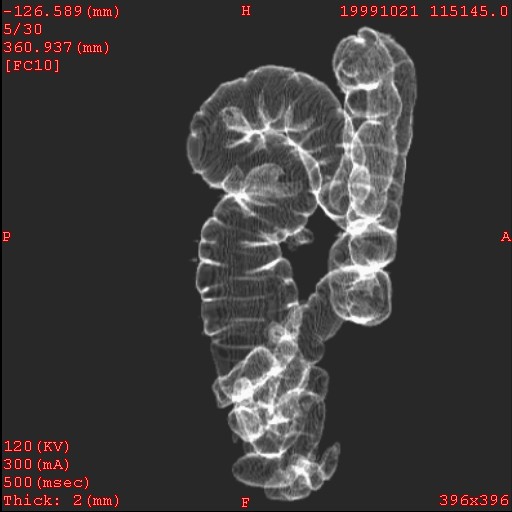

Diverticulosis: Virtual

colonography, 47y, femele

Plain CT, 0.5-sec/rotation,

2-mm x 4, 120kV, 150mAs

Ray sum display, RAO view

Data acquired and processed

by Kei Takase M.D.